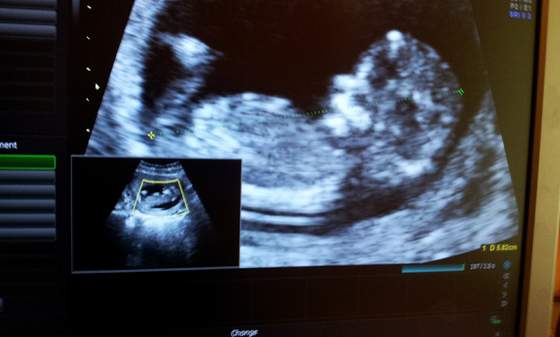

My też już po wizycie. I wszystko w jak najlepszym porządku. Dzidzia ma prawie 6 cm. Przezierność karkowa i kość nosowa prawidłowa-to mnie naprawdę mega cieszy. Miałam robione USG na jakimś wypaśnym sprzęcie. Że niby wszystko w HD i w ogóle. Mój Marcin oczywiście nakręcił filmik z USG i porobił chyba z 10 zdjęć Dzidzi. Pan Doktor ładnie współpracował - na tyle, że nawet w pewnym momencie udało nam się uchwycić jakby Dzidzia przybijała nam piątkę. Ogólnie wizyta bardzo miła. Następna 17 listopad.

A oto zdjęcia Szkraba:

C360_2011-10-2015-55-43.jpgC360_2011-10-2015-56-19.jpg